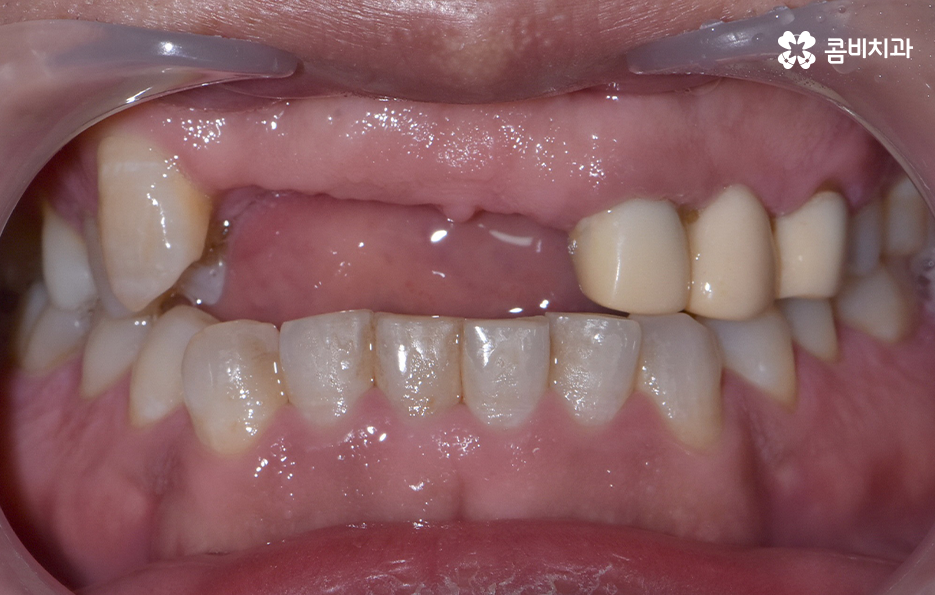

앞니가 사라진 자리로 혀가 자꾸만 가고, 말하려 할 때마다 공기가 앞니가 있어야 할 공간으로 빠져나가 발음이 어색해졌어요

웃음이 나올 때마다 본능적으로 입술로 그 빈틈을 가리게 되면서 이 변화에 적응하고 싶지 않았어요

처음에는 임플란트라는 단어를 떠올리는 것만으로도 부담스러웠어요 앞니처럼 심미적인 부분이 크게 작용하는 위치에 인공 치아을 심어 사람의 치아와 똑같이 만드는 과정이 쉽게 느껴지지 않았어요

이렇게 앞니가 상실되면 심미적, 기능적 불편이 크기 때문에 많은 분들이 앞이빨 임플란트 과정을 거치게 되는데 앞니 임플란트는 어금니와는 다른 부분에서 좀더 정교한 치료가 필요하며 앞니 부위는 뼈가 얇고 심미성이 중요한 부위라는 점에서 잇몸 라인, 앞니의 각도, 심미성, 주변 치아와의 조화까지 모두 맞아야 자연스럽게 보이므로 정교한 치료의 중요성이 더 높은 부위라고 할 수 있어요

또한 앞니는 잇몸의 모양이 심미성에 큰 영향을 주는데, 잇몸이 얇으면 임플란트가 비쳐 보이거나 잇몸 라인이 붕괴될 위험이 있어서 이런 경우에는 잇몸 두께를 보강하는 잇몸 이식술이 필요할 수 있으며 앞이빨 임플란트 과정 뿐 아니라 치료 후에도 잇몸 관리는 앞니 임플란트의 수명, 심미적인 유지에 있어서 중요한 요소라고 볼 수 있었어요